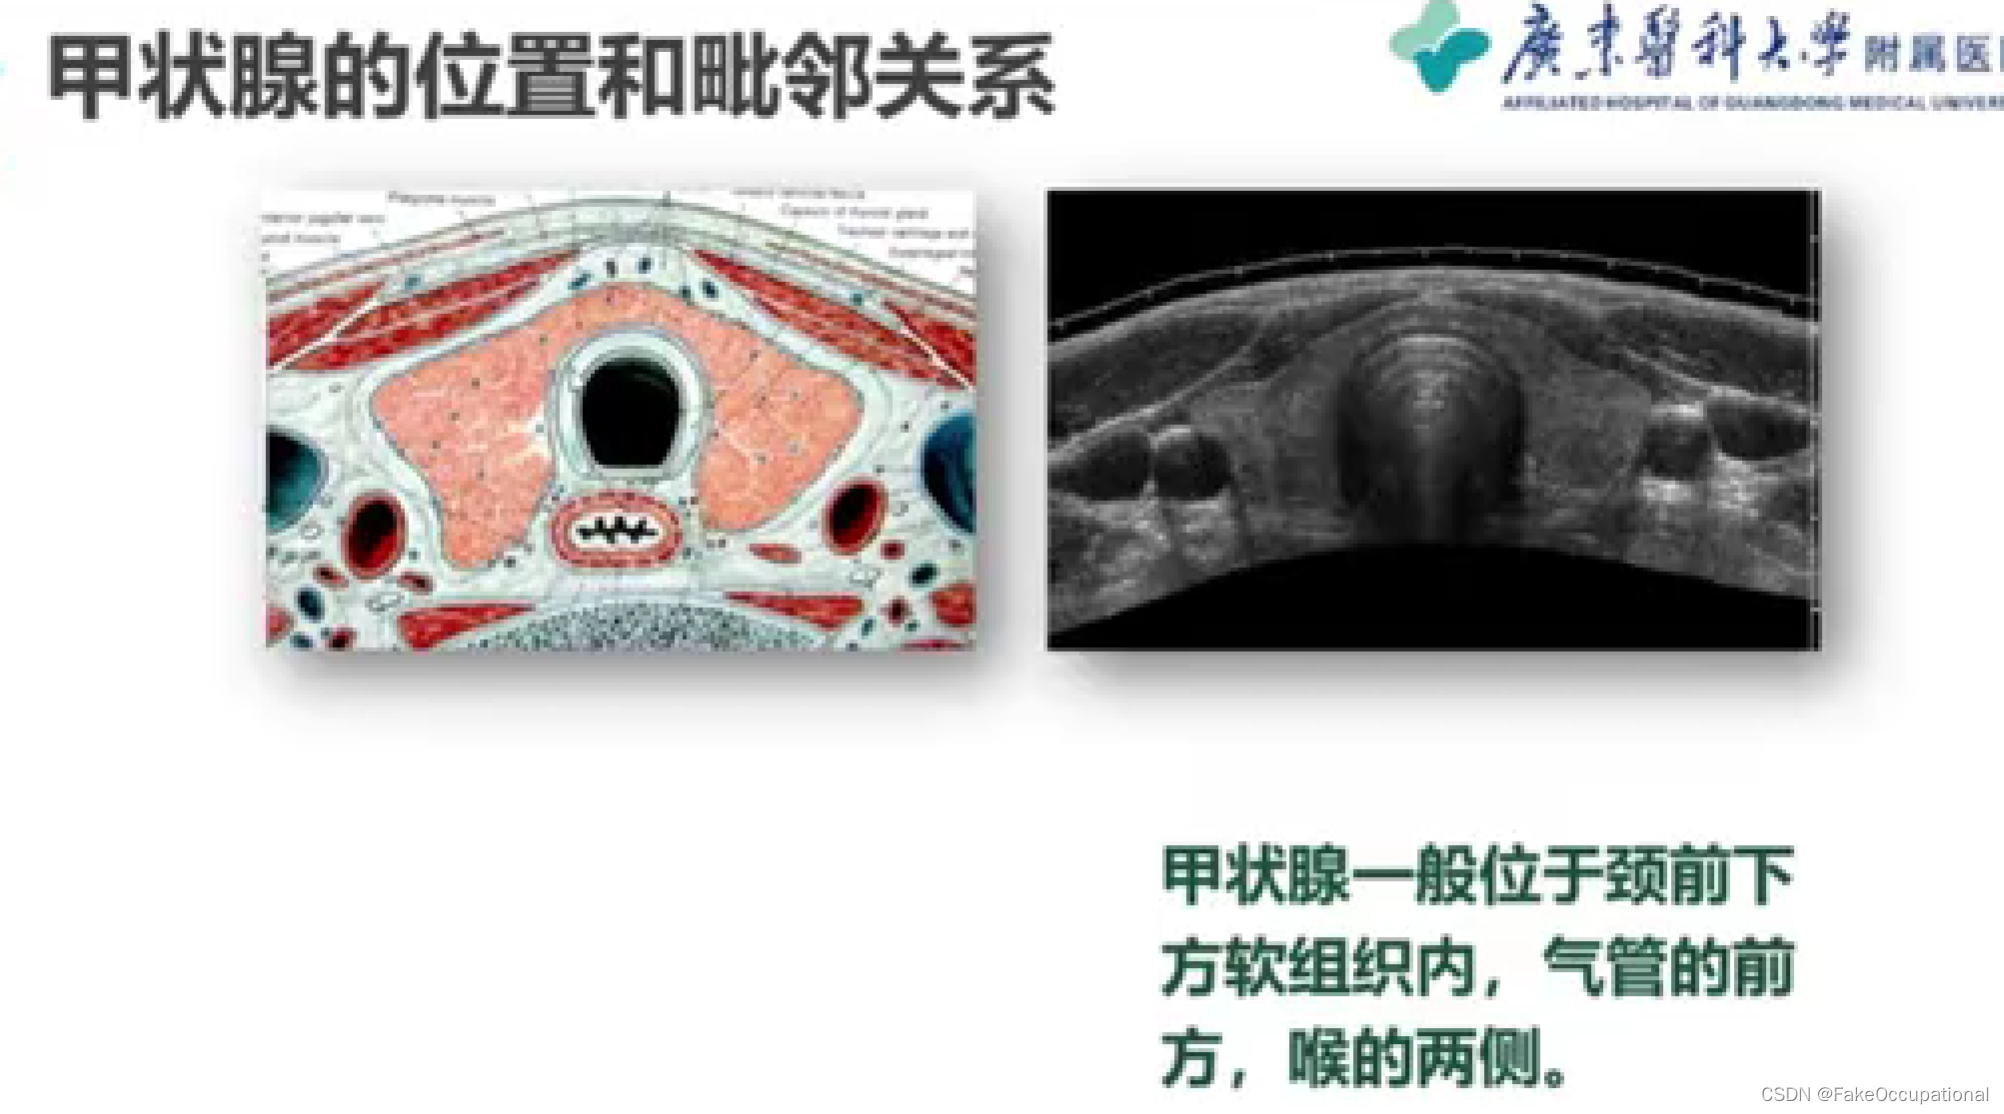

甲状腺超声